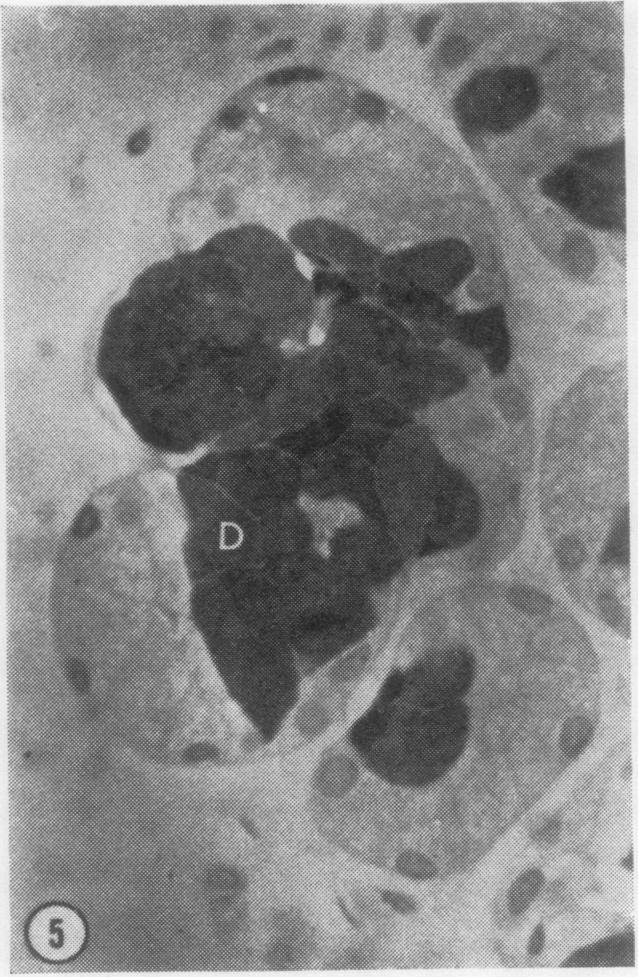

The morphology of the labial salivary glands in subjects with and without cystic fibrosis has been studied by light and electron microscopy. The terms ;light' cell, ;dark' cell, ;clear' cell, and ;myoepithelial' cell are used to describe the four cell types distinguished at the level of the electron microscope. The dark cells were found to stain specifically with alcian blue at and above pH 1.0, and the light cells to stain specifically using the periodic acid-Schiff (PAS) technique. This staining reaction suggests that an acidic mucosubstance is being produced by the dark cells and a neutral mucosubstance by the light cells. While no marked morphological differences were observed in the labial glands of patients with cystic fibrosis when contrasted with normal controls, it was observed that the cells from patients with cystic fibrosis contained quantitatively more mucus.

通过光学显微镜和电子显微镜对患有和未患有囊性纤维化的受试者的唇唾液腺形态进行了研究。术语“亮”细胞、“暗”细胞、“透明”细胞和“肌上皮”细胞用于描述在电子显微镜水平上区分出的四种细胞类型。发现暗细胞在pH 1.0及以上时与阿尔辛蓝特异性染色,亮细胞使用过碘酸希夫(PAS)技术特异性染色。这种染色反应表明暗细胞产生酸性粘多糖物质,亮细胞产生中性粘多糖物质。虽然与正常对照相比,囊性纤维化患者的唇腺未观察到明显的形态学差异,但观察到囊性纤维化患者的细胞中粘液的含量在数量上更多。